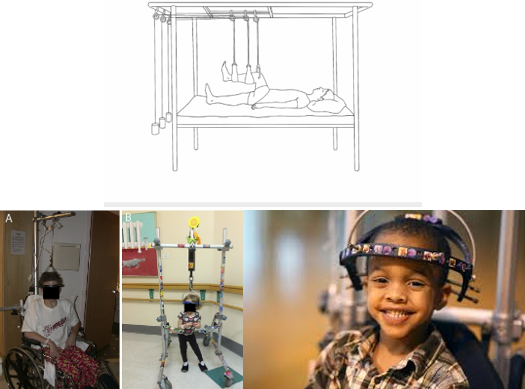

Traction

Uses:

Reduce and/or immobilize a fracture

Align an injured extremity

Allow the extremity to be restored to its normal length

May also reduce pain by decreasing the incidence of muscle spasms.

Extension by a pulling force may be used.

The type of traction used depends on the child’s age, the condition of the soft tissue, and the type and degree of displacement of the fracture:

Manual Traction:

Applied to the body part by hand, placed distally to the fracture site.

Skin Traction:

Pulling mechanisms are attached to the skin with adhesive material or elastic bandage.

Skin must be intact!

Skeletal Traction:

Applied directly to the skeletal structure by a pin, wire, or tongs inserted into or through the diameter of bone distal to the fracture.

Skin Traction

Buck’s Traction:

Reduces femur fractures.

Also used for contractures of the hip or knee.

Force is delivered through a traction boot or skin traction in a straight line.

**Skin must be intact!

Skeletal Traction

90-90 Traction:

Reduces femur fractures.

Pins are placed through the distal femur; traction is applied through pins only.

Huge risk for infection and pressure sores.

Nursing Considerations:

Regular pin care per policy.

Diversional activities

Frequent assessment of the peripheral neurovascular system.

Encourage patients to use their unaffected extremities.

Monitor U/O & BM.

Ensure adequate nutrition and hydration.

Encourage incentive spirometry use.

Halo Traction:

Used for fractures or injuries of the cervical spine.

First step in correcting severe scoliosis, kyphosis, and other spinal deformities.

A ring surrounds the head, and pins are attached to the outer portion of the skull.

Nursing Care of a Patient in Traction

Assessment of the 5 Ps

Maintain traction and alignment

Monitor weights and ropes:

All weights should hang freely; they should not rest on the ground or the bed.

Nurses do not adjust the weights.

Prevent skin breakdown using proper padding

Prevent complications

Provide pain management and comfort measures

Exercise unaffected extremities

Encourage deep breathing

Monitor for constipation or urinary stasis

Provide distraction

Enlist Child Life Services (CLS)